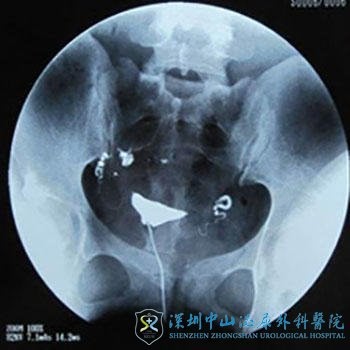

输卵管造影

输卵管造影是目前输卵管积水的检查方法中简便可靠的方法。